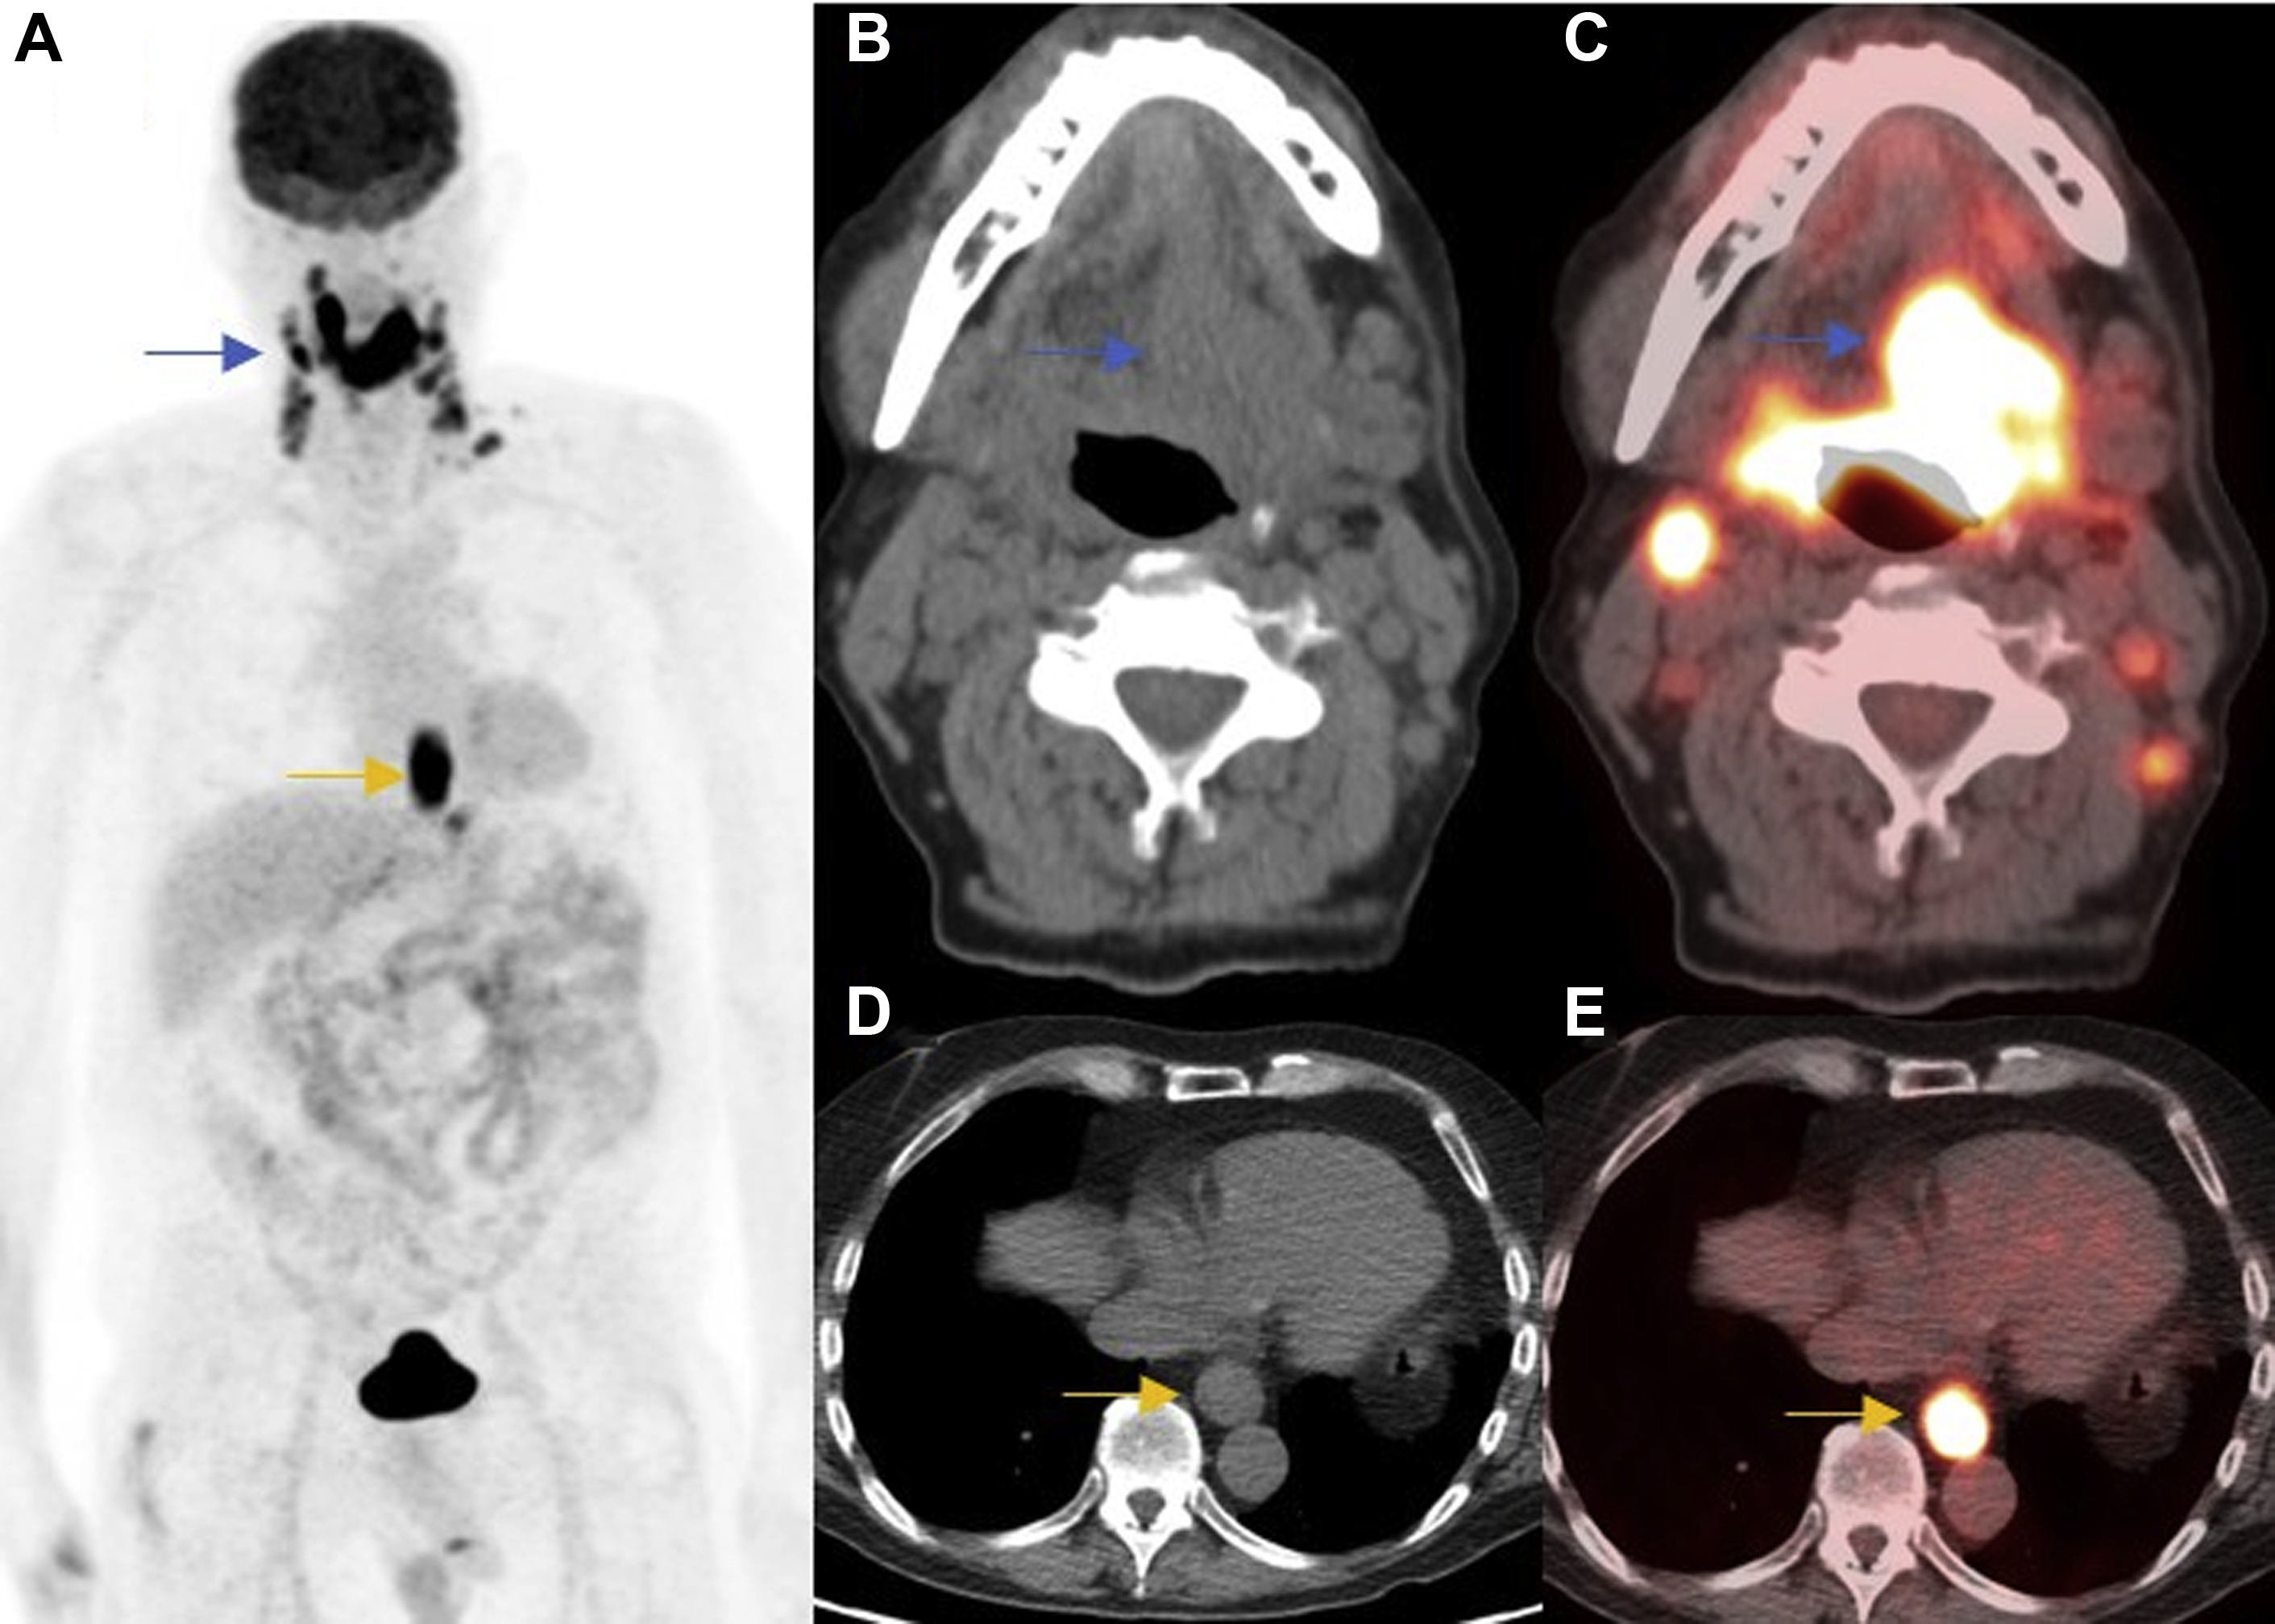

Cancers Free FullText PETCT in Clinical Adult Oncology I

From www.mdpi.com

From www.frontiersin.org